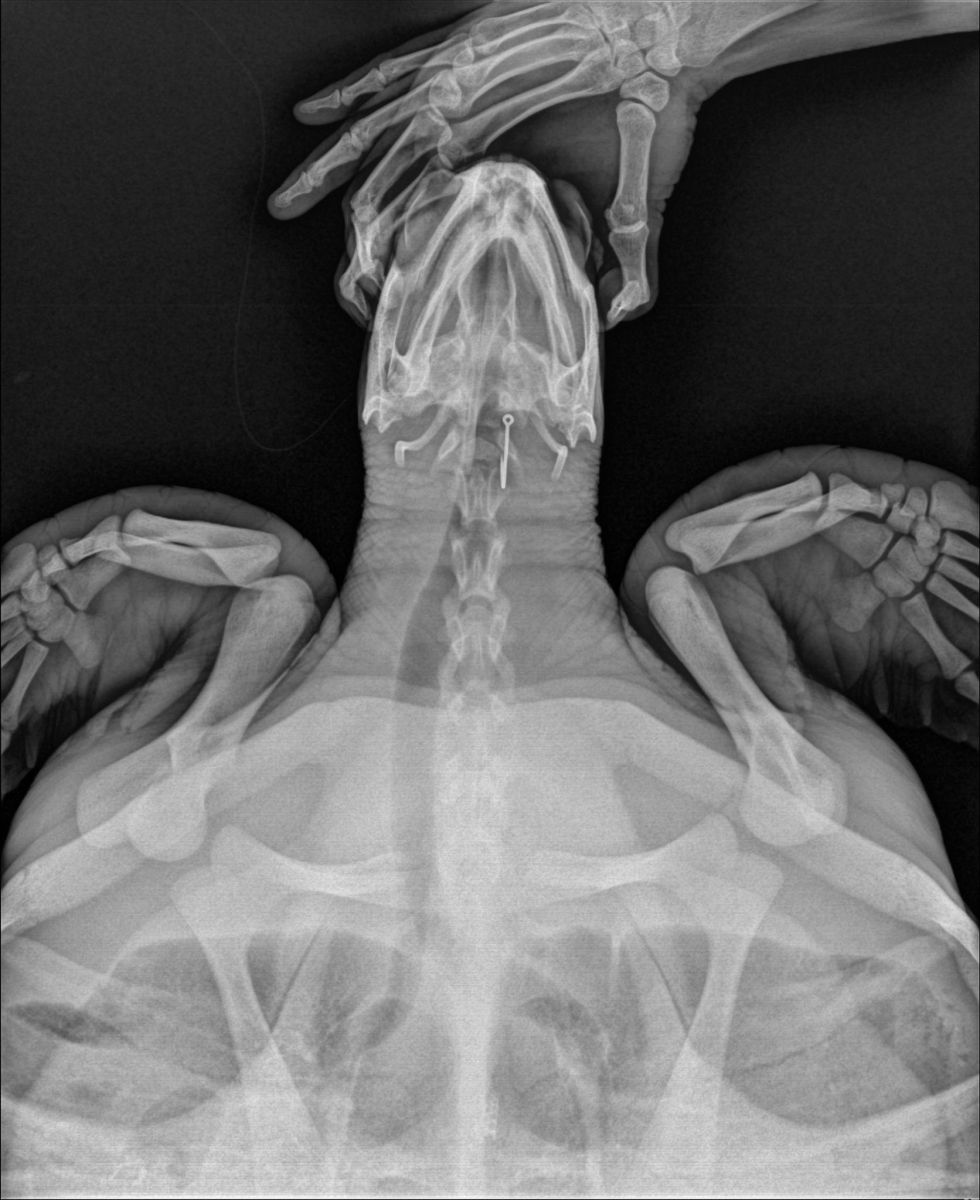

เจ้าหน้าที่ทำการตรวจร่างกายพบเป็นเต่าตนุ (Chelonia mydas) อยู่ในช่วงวัยรุ่น ขนาดกระดองกว้าง 50 เซนติเมตร ขนาดกระดองยาว 53 เซนติเมตร น้ำหนักประมาณ 17.5 กิโลกรัม ความสมบูรณ์ของร่างกายอยู่ในระดับสมบูรณ์ปกติ (BCS 3/5) สภาพภายนอกไม่พบบาดแผล มีเพรียงขนาดเล็กเกาะบริเวณกระดองท้อง สภาพร่างกายแข็งแรง ตอบสนองดี ตรวจพบเส้นเอ็นติดอยู่ที่บริเวณช่องปาก สัตวแพทย์ได้ทำการตรวจร่างกายโดยการถ่ายภาพรังสี พบเบ็ดตกปลาติดอยู่ภายในช่องปาก 1 ชิ้น

จากนั้นสัตวแพทย์ได้พิจารณาทำการวางยาซึมและนำเบ็ดตกปลาออกโดยทันที ซึ่งสามารถนำตะขอเบ็ดออกได้ด้วยดี โดยได้ให้การรักษาและอนุบาลพักฟื้น ณ ศูนย์ช่วยชีวิตสัตว์ทะเลหายากสิรีธาร ศวอบ. เพื่อฟื้นฟสุขภาพก่อนจะปล่อยกลับสู่ธรรมชาติต่อไป